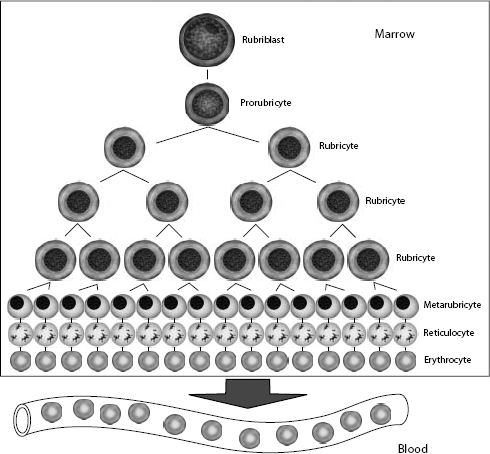

The committed erythroid precursor undergoes up to five mitotic divisions over 5 days. The earliest recognizable erythroid precursor is the rubriblast, followed by differentiation sequentially to the prorubricyte, rubricyte, metarubricyte, polychromatophilic erythrocyte, and the mature erythrocyte (Fig. 1.2). Erythroid maturation correlates with a decrease in EPO receptors and an increase in transferrin receptors on the surface of red cell precursors. Transferrin receptors allow for incorporation of iron into erythrocytes, for hemoglobin synthesis. Hemoglobin comprises four globin chains, each bound to a heme molecule containing iron. Hemoglobinization of the red cell cytoplasm is most active during the rubricyte stage. Also, cell division stops during the rubricyte stage as hemoglobinization nears completion and the nucleus condenses. At the end of the metarubricyte stage, the pyknotic nucleus is extruded and phagocytized by local macrophages.

Figure 1.2 Erythrocyte kinetics. After stimulation by erythropoietin (EPO), cells in the committed erythroid compartment differentiate into rubriblasts, followed by mitotic division and maturation to mature erythrocytes.